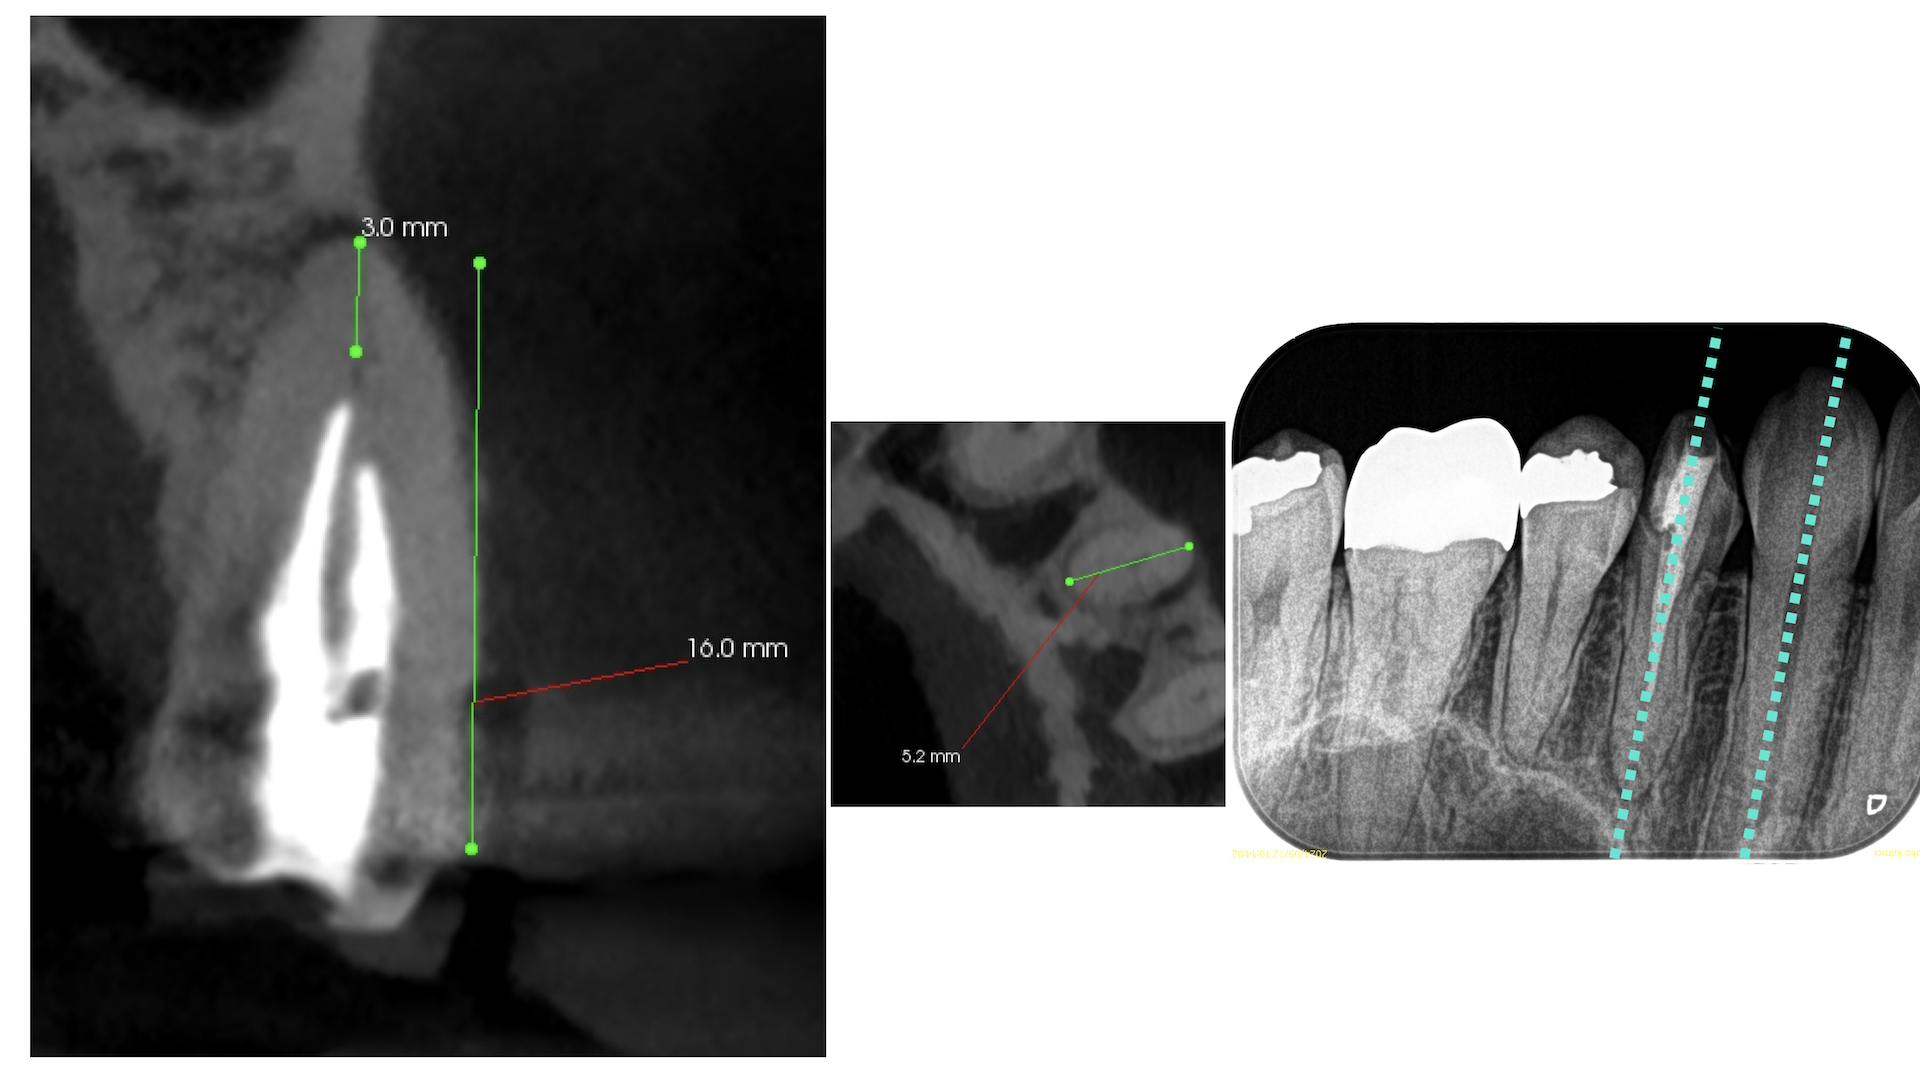

その際は、

それほど難しいApicoectomyではない、とわかる。

CBCTを分析すれば、だ。

#12 Apicoectomy(2025.3.7)

Apexの位置のOsteotomyすると、そのApexは容易に発見できた。

根尖を3mm切断し、メチレンブルーで染色した。

問題はない。

逆根管形成し、逆根管充填した。

ペントロンジャパンの

エンドセム MTA クイックペースト R

で逆根管充填した。

いわゆるシーラー逆根管充填(そんな言葉があるのか?)である。

術後にPA, CBCTを撮影した。